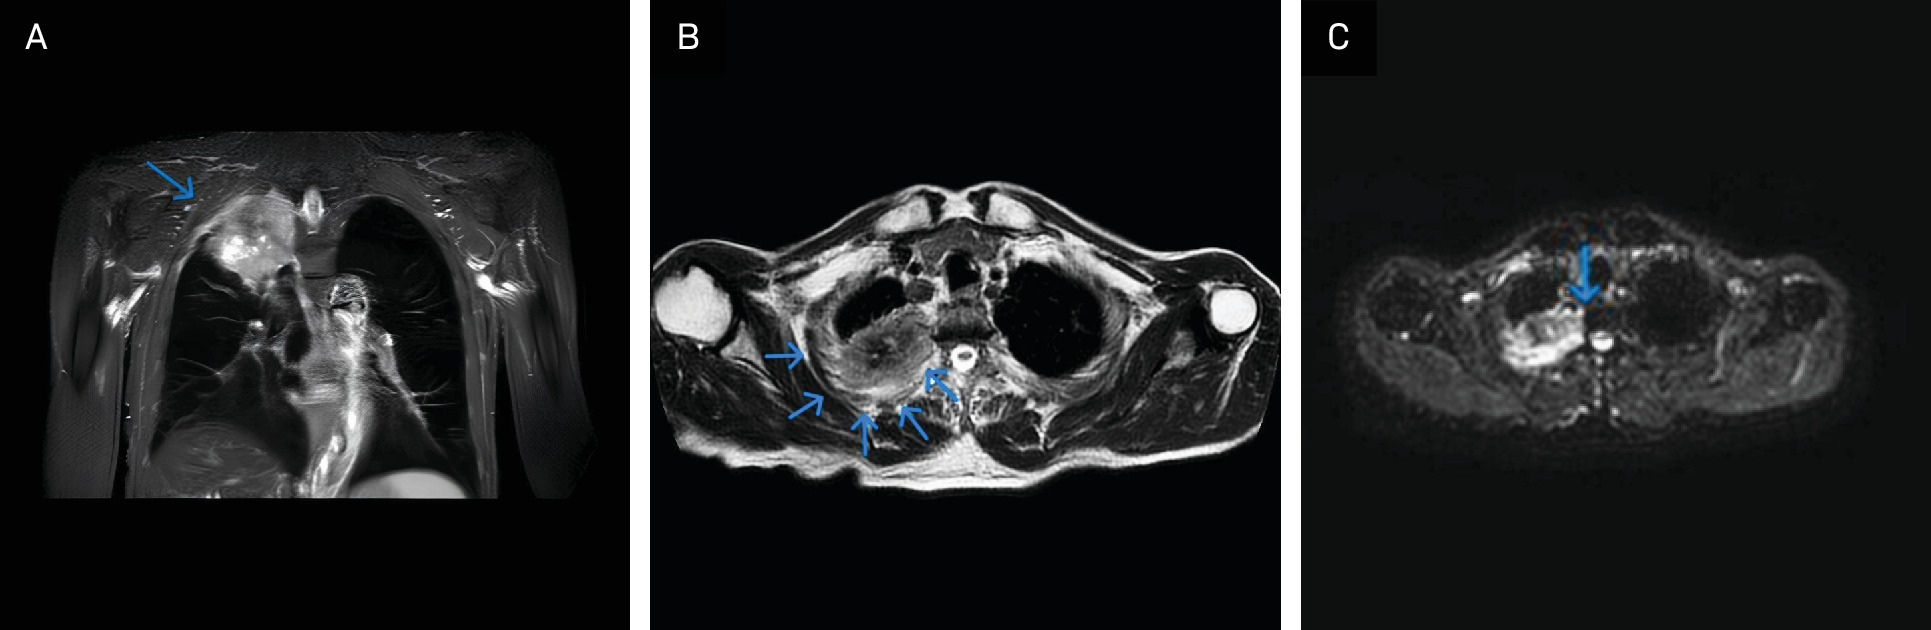

The first relevant imaging evaluation was performed in November 2023 because of suspected Pancoast syndrome. MRI (Figure 1A-C) revealed a mass measuring 7.2 cm (axial) × 6.8 cm (coronal) × 8.9 cm (sagittal) in the right upper lobe, infiltrating the ipsilateral second through 4th ribs and abutting the second through 4th thoracic vertebrae.